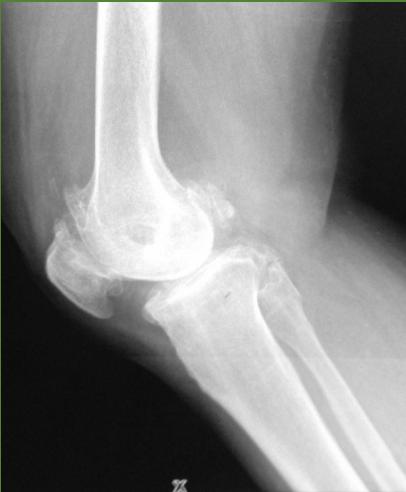

Tennis Elbow (Lateral Epicondylitis)

Have you ever heard of tennis elbow or suffered from elbow pain? Continue reading to learn about this condition and a new study that may change the way we approach treating this problem.

Steroid injection for tennis elbow

INJECTION TARGET Therapeutic agent is injected between the bone and the common extensor tendon (about 1 cm anterior to the lateral epicondyle with the elbow in a flexed position)